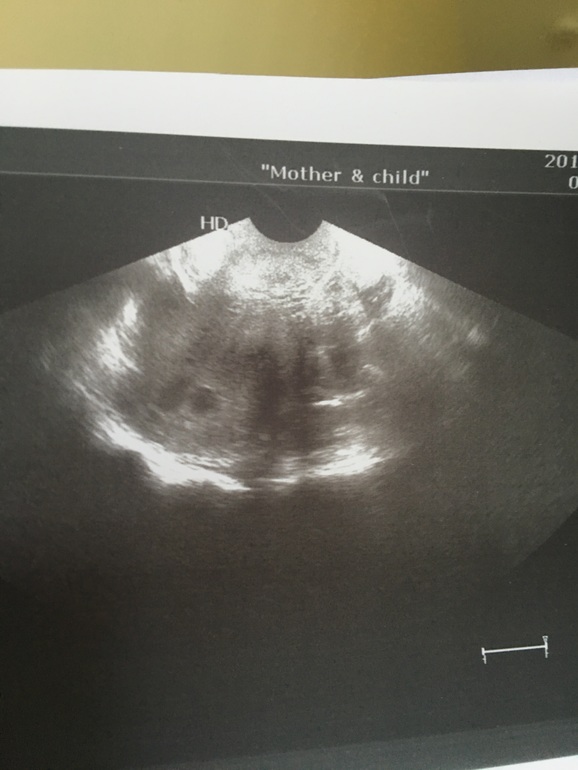

Протоколы ЭКО (Все о них, все об этом периоде+Гиперстимуляция)Девочки, помогите, была сегодня на узи, увидели 1 пя и жм и рядом ещё какое-то образование((( подсаживали одного. Врач сначала выкрикнула -двойня! Но потом поняли что нет. Что это - она не знает, назначила узи аж на 5 сентября. И как до него дожить?

Справа по меньше - пя, а что слева?((((

У меня с одной клеточкой двойня получилась. Тоже одного подсаживали. Правда однояйцевая, в одном ПЯ, поэтому по-другому выглядела, чем у вас. По вашему ущи я бы тоже заподозрила двойню, только разнояйцевую. А вдруг и вас самих тоже получилось помимо Эко? Чудеса случаются. А вообще единственный выход ждать до следующего узи. Или переделать в другом месте ещё раз.